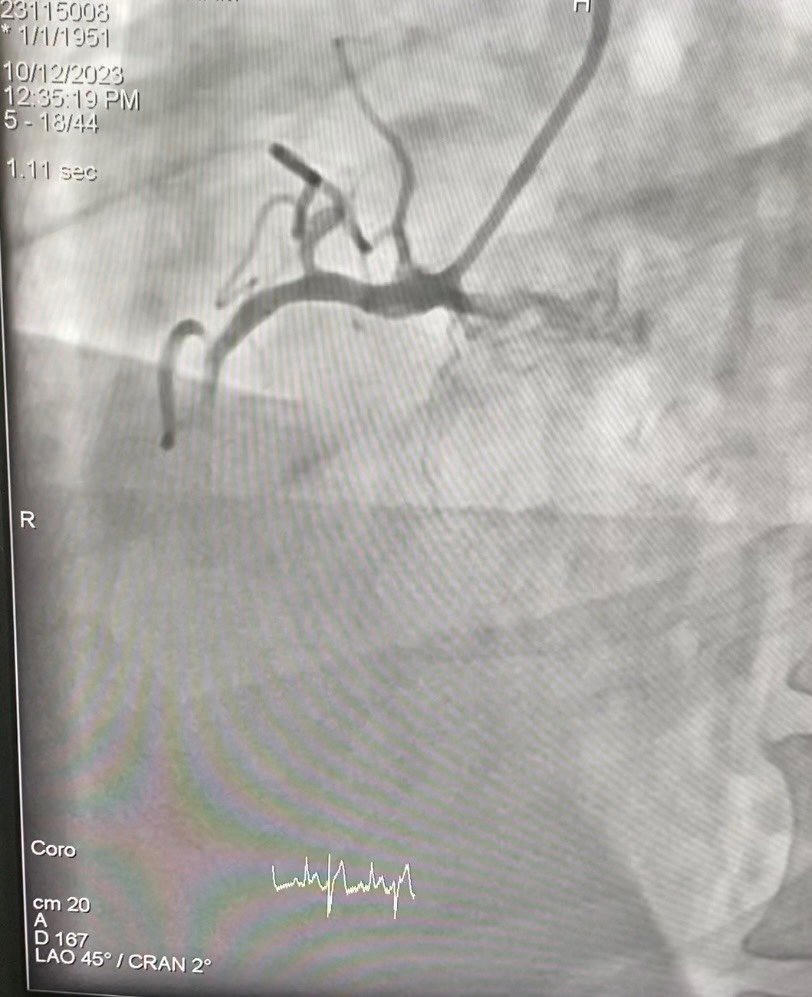

Qua thăm khám ban đầu, các bác sĩ cho biết, bệnh nhân tỉnh, tiếp xúc tốt, than đau tức ngực vùng sau xương ức nhiều kèm khó thở. Có hình ảnh nhồi máu cơ tim cấp thành dưới, nhồi máu cũ thành trước

Khi tiến hành siêu âm tim tại giường ghi nhận suy tim, chức năng tâm thu thất trái giảm EF=30%. Bệnh nhân được chẩn đoán là nhồi máu cơ tim cấp thành dưới giờ thứ 2, nhồi máu cơ tim cũ thành trước đã đặt 2 stent mạch vành, suy tim phân xuất tống máu giảm, ĐTĐ type II.

Bệnh nhân được chẩn đoán là nhồi máu cơ tim cấp thành dưới giờ thứ 2. Ảnh: BVCC |

Ngay sau đó, bệnh nhân được chỉ định chụp can thiệp mạch vành cấp cứu. Kết quả là động mạch liên thất trước (LAD) tắc trong stent ở đoạn 2, động mạch vành phải (RCA) tắc cấp trong stent ở đoạn 2, ĐM mũ (LCx) không hẹp. Bệnh nhân được can thiệp cấp cứu với 1 stent, sau can thiệp dòng máu lưu thông qua động mạch vành phải(RCA) tốt (TIMI III), sau 30 phút bệnh nhân hết đau ngực.